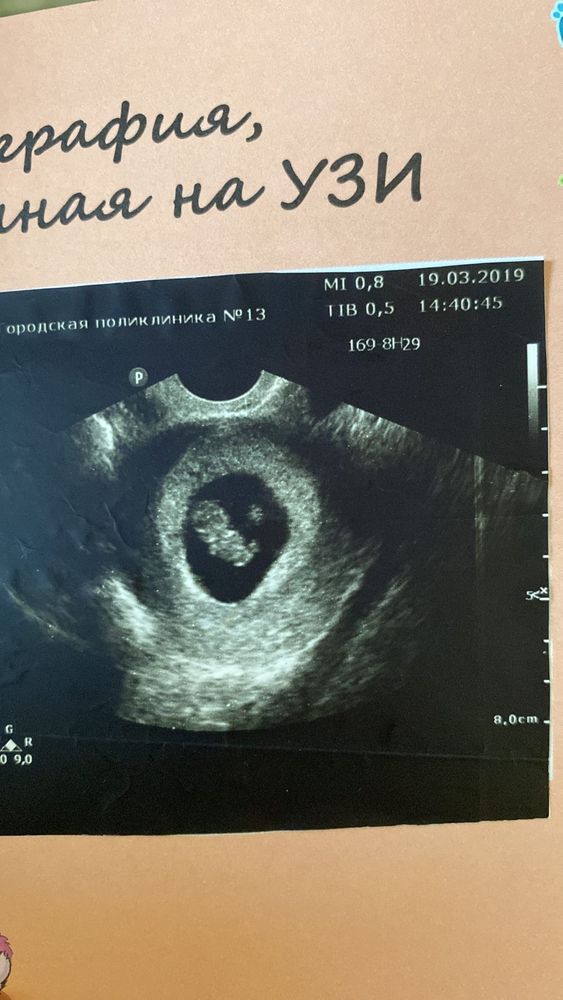

Изображение Ровно 8 недель

Если допускает, что у вас могла быть поздняя овуляция, то могут быть и 5 недель. На таком сроке обычно эмбрион и сб не видно ещё. Обычно эмбрион и сб появляются в 6-7 недель.

В 5 недель ничего не увидели. Через 3 дня желточный мешочек увидели и пустое плодное яйцо. В 6 недель увидели эмбрион, но не было сердцебиения. Решили, что может быть замершая. Делали УЗИ каждые 3 дня. В 7 недель услышали сердцебиение.